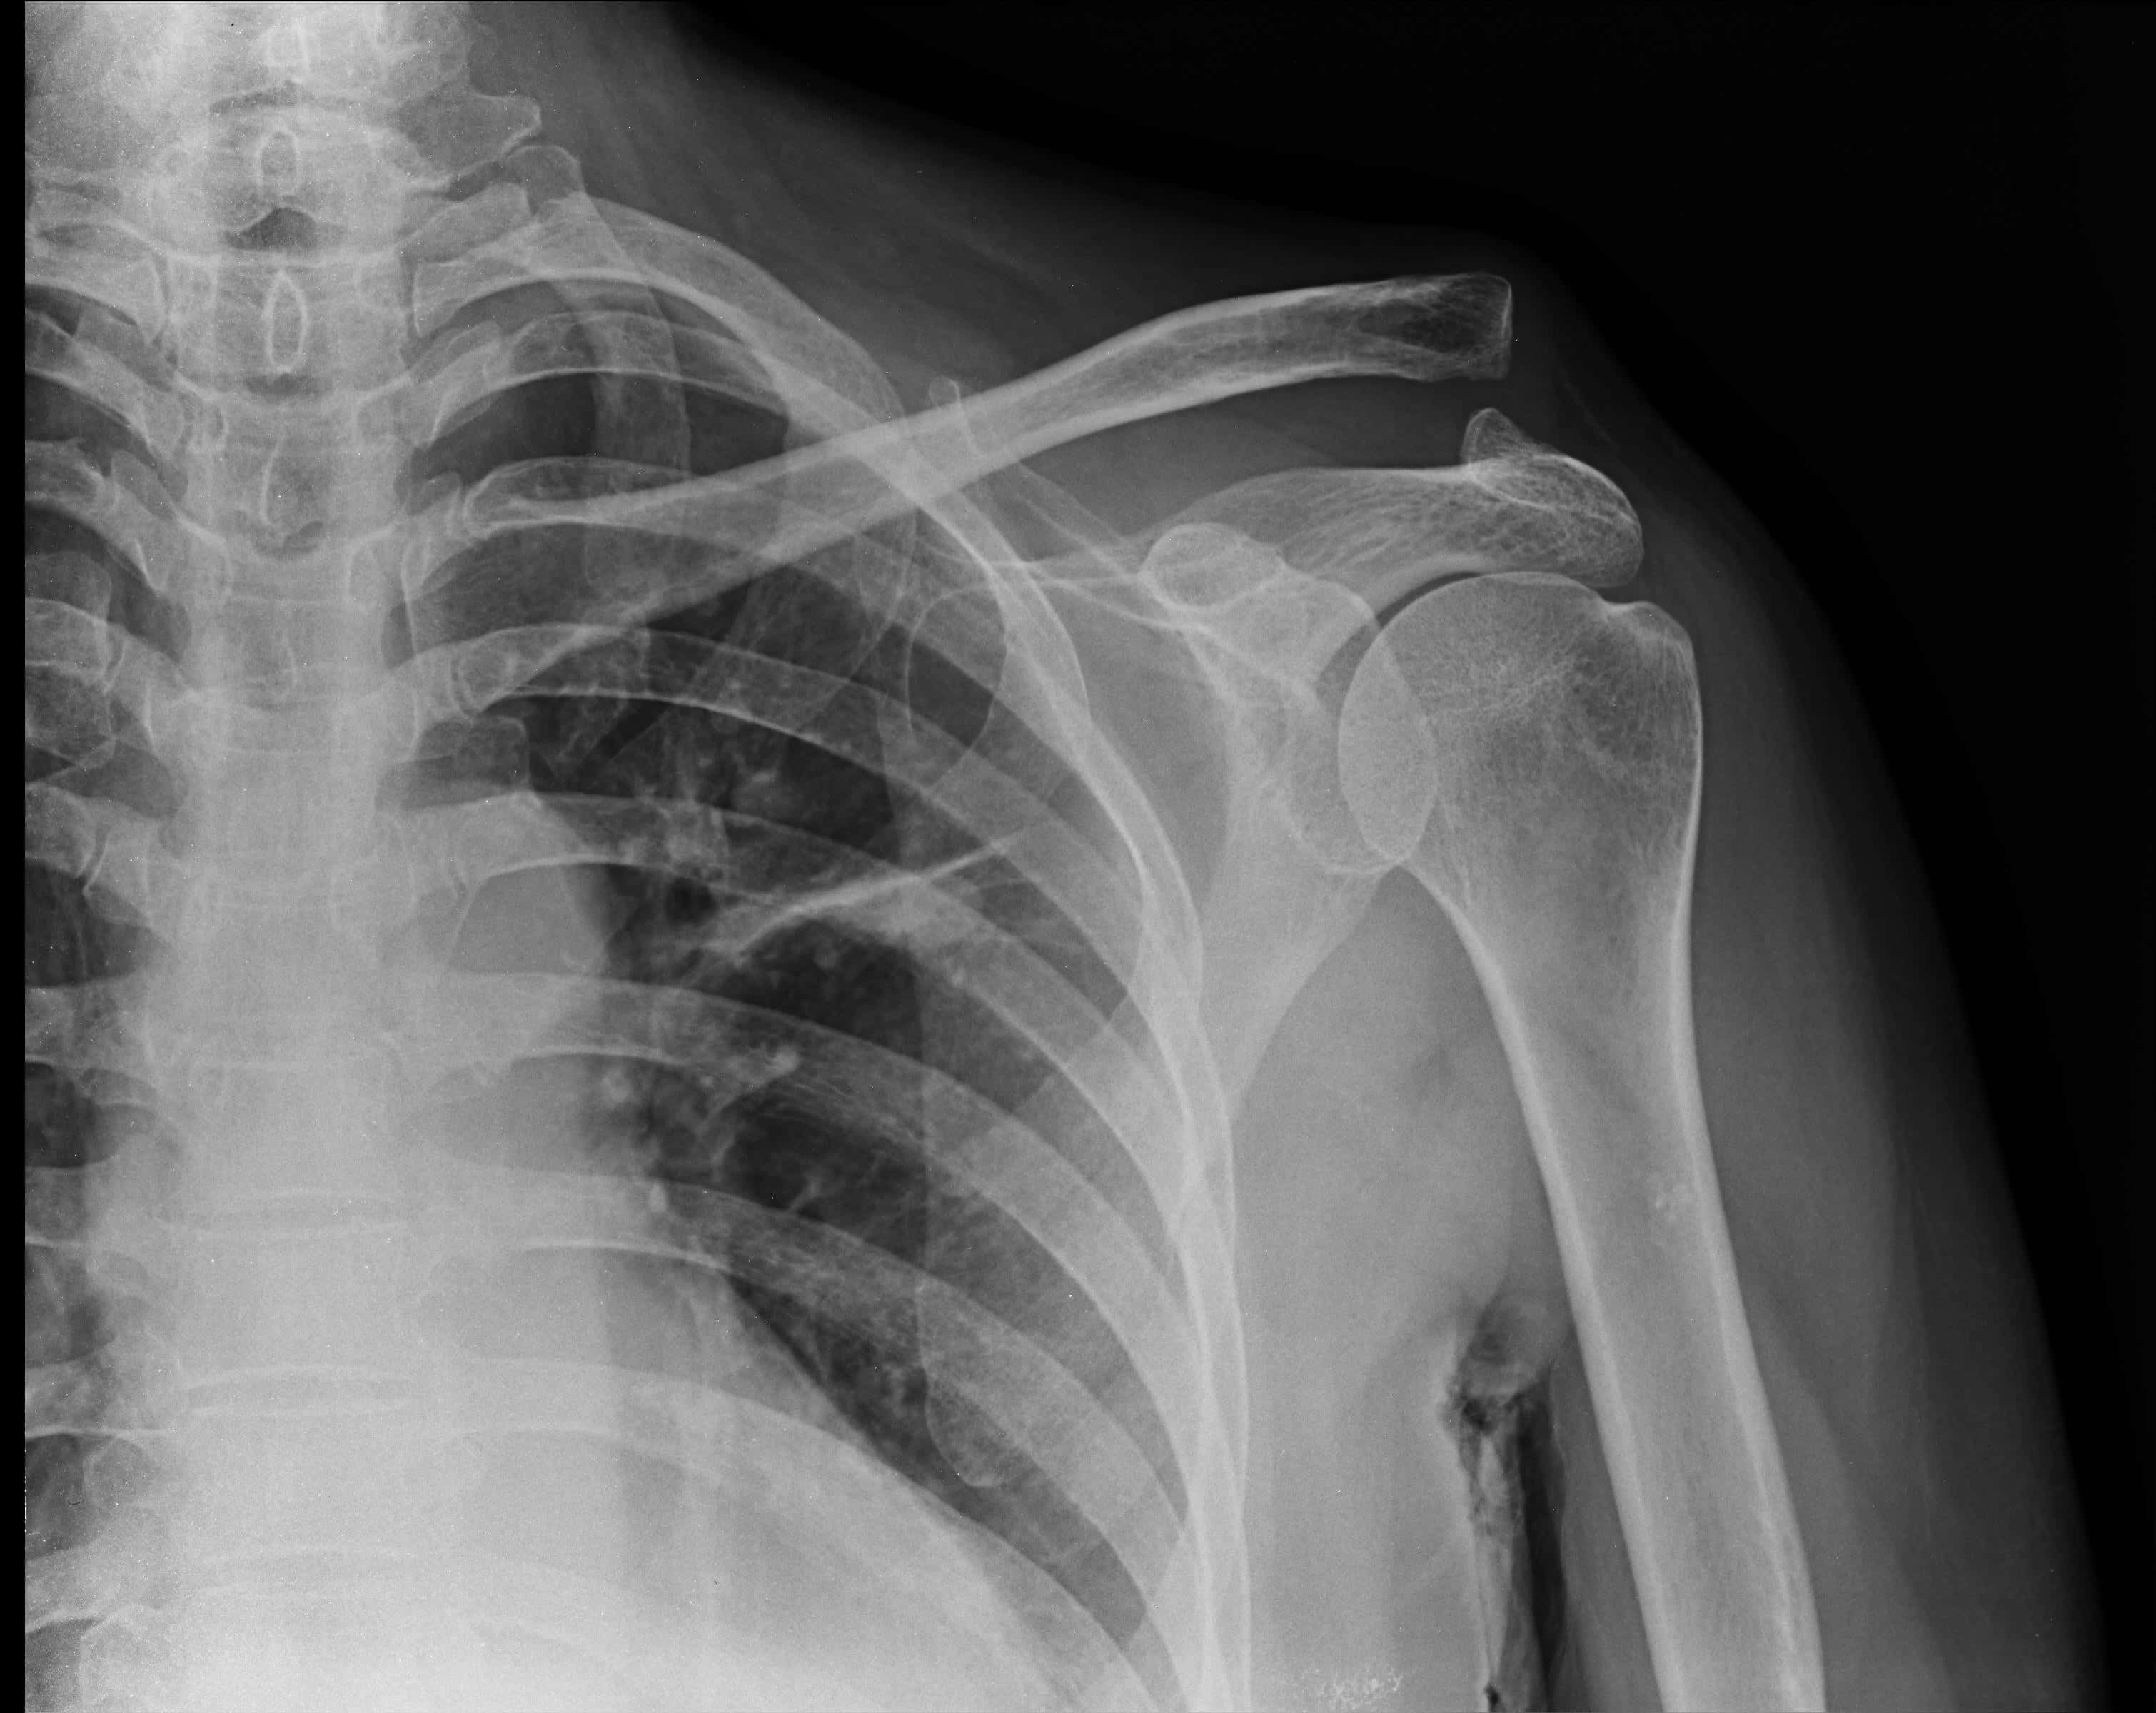

áşááźáŽá¸ ááŻááŻáśá¸áážáŹ áááááŻááşááŤááşáᏠáááźááşá¸áááŤááşááźá

áşááąáŤáşááŹáááŻááşááŤáááşá ááŤááąáááˇáş áááŤáááś ááŻááŻáśá¸ááŹááťááşááźááşá¸áᏠáááşáááşá¸áážáŹááźá

áŹá¸ááąááá˛áˇ ááŻááŻáśá¸ááŹááťááşááźááşá¸áᏠáááşáááşá¸áážáŹááźá

áááşáááşá¸áážáŹáážááá˛áˇ áĄáŹááŻáśááźáąáŹáĄááááśáááźáŽááááááŻááşááźáŽáááŻáááş ááŹááťááşáážáŻá ááŻááŻáśá¸áĄáá ááąáŹááşááŹáááŻááşááźáŽá¸ áĄáŹá¸áááşá¸ááťáąáŹáˇáá˝áąááźááşá¸áááŻáśááťááşááźááşá¸áá˝áąáááąáŹáˇ áááşáááťážáąáŹááşááŻáśá¸áážáŹ ááťáśáˇáážáśáˇáá˝áŹá¸áááŻááşááŤáááşá

ááŽáááŻáĄááźáąáĄááąááᯠááąá¸áááŹááąáŤááŹááá˛áˇ âáááşáááşá¸áĄáŹááŻáśááźáąáŹáááşááźááşá¸â áááŻáˇ ááąáŤáşááąáŤáşááąáˇáážáááźáŽá¸ áĄáąáŹááşááąáŹáşááźá፠ááąáŹááŤááášáááŹáá˝áąááᯠááśá